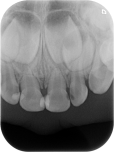

离体牙

4.哪些口腔问题需要拍片呢?

像拔智齿、补牙、做根管治疗、牙周病、种植牙、牙齿矫正等等都需要拍片。牙片基本属于常规检查。